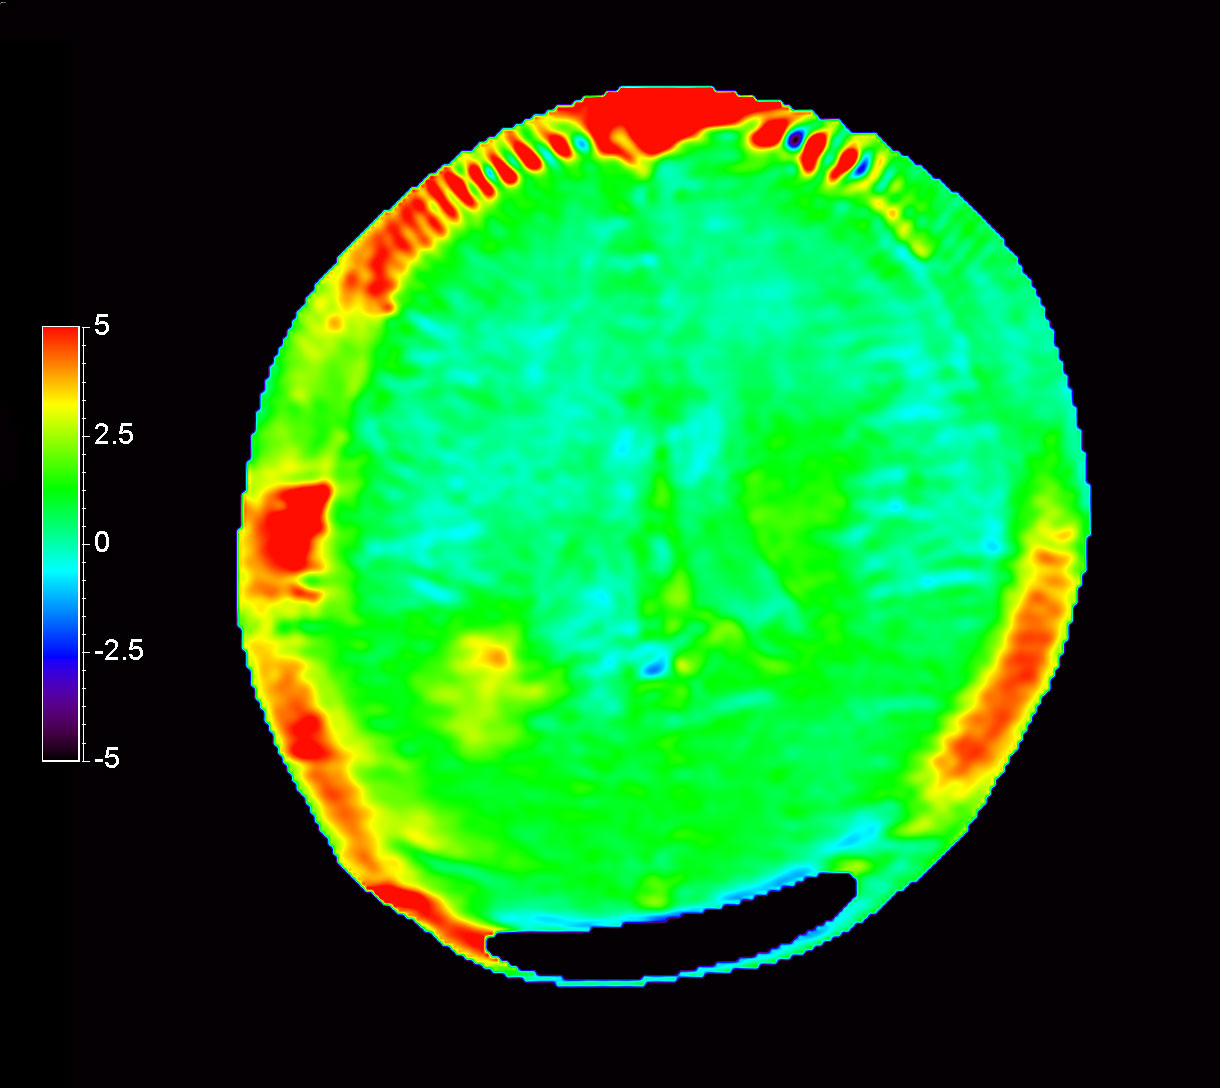

Axial 3D APT